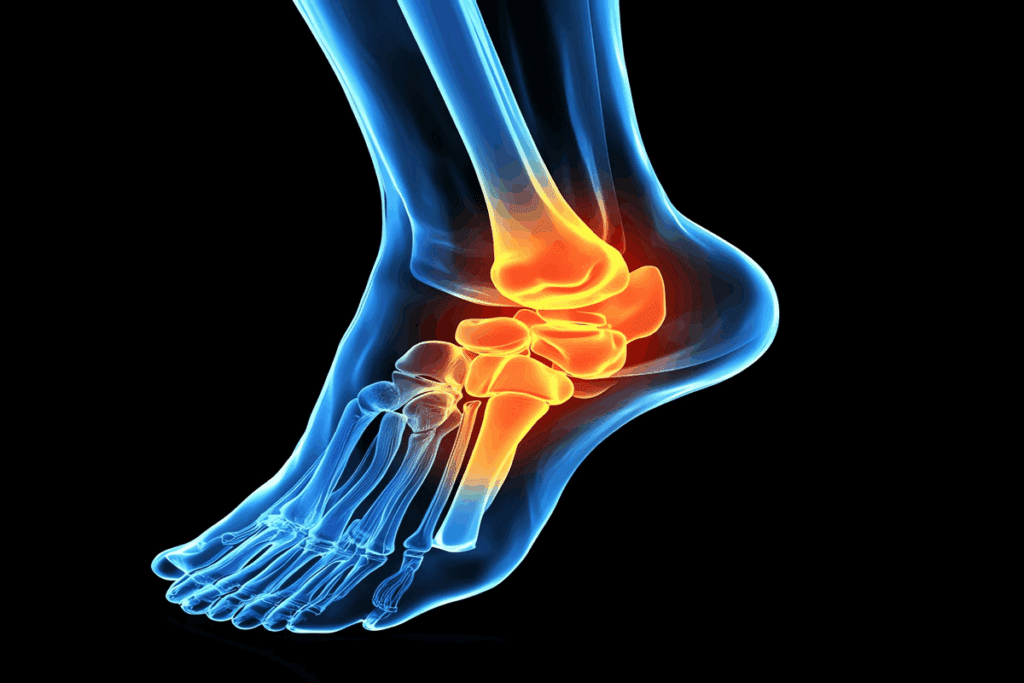

Lower Extremity Tendonitis Diagnosis

Lower body tendonitis, like in the hip, knee, or ankle, has its own challenges. For example, Achilles tendonitis needs a detailed look at the tendon sheath and nearby tissues.

| Location | Common Tendonitis Types | Diagnostic Considerations |

| Hip | Gluteus medius tendonitis | Check for hip abductor weakness, feel for tenderness |

| Knee | Patellar tendonitis (jumper’s knee) | Look at the knee extensor mechanism, feel for pain |

| Ankle | Achilles tendonitis | Check for swelling, pain when bending the ankle |

Knowing how to diagnose tendonitis in different parts of the body helps doctors. This leads to better care and results for patients.